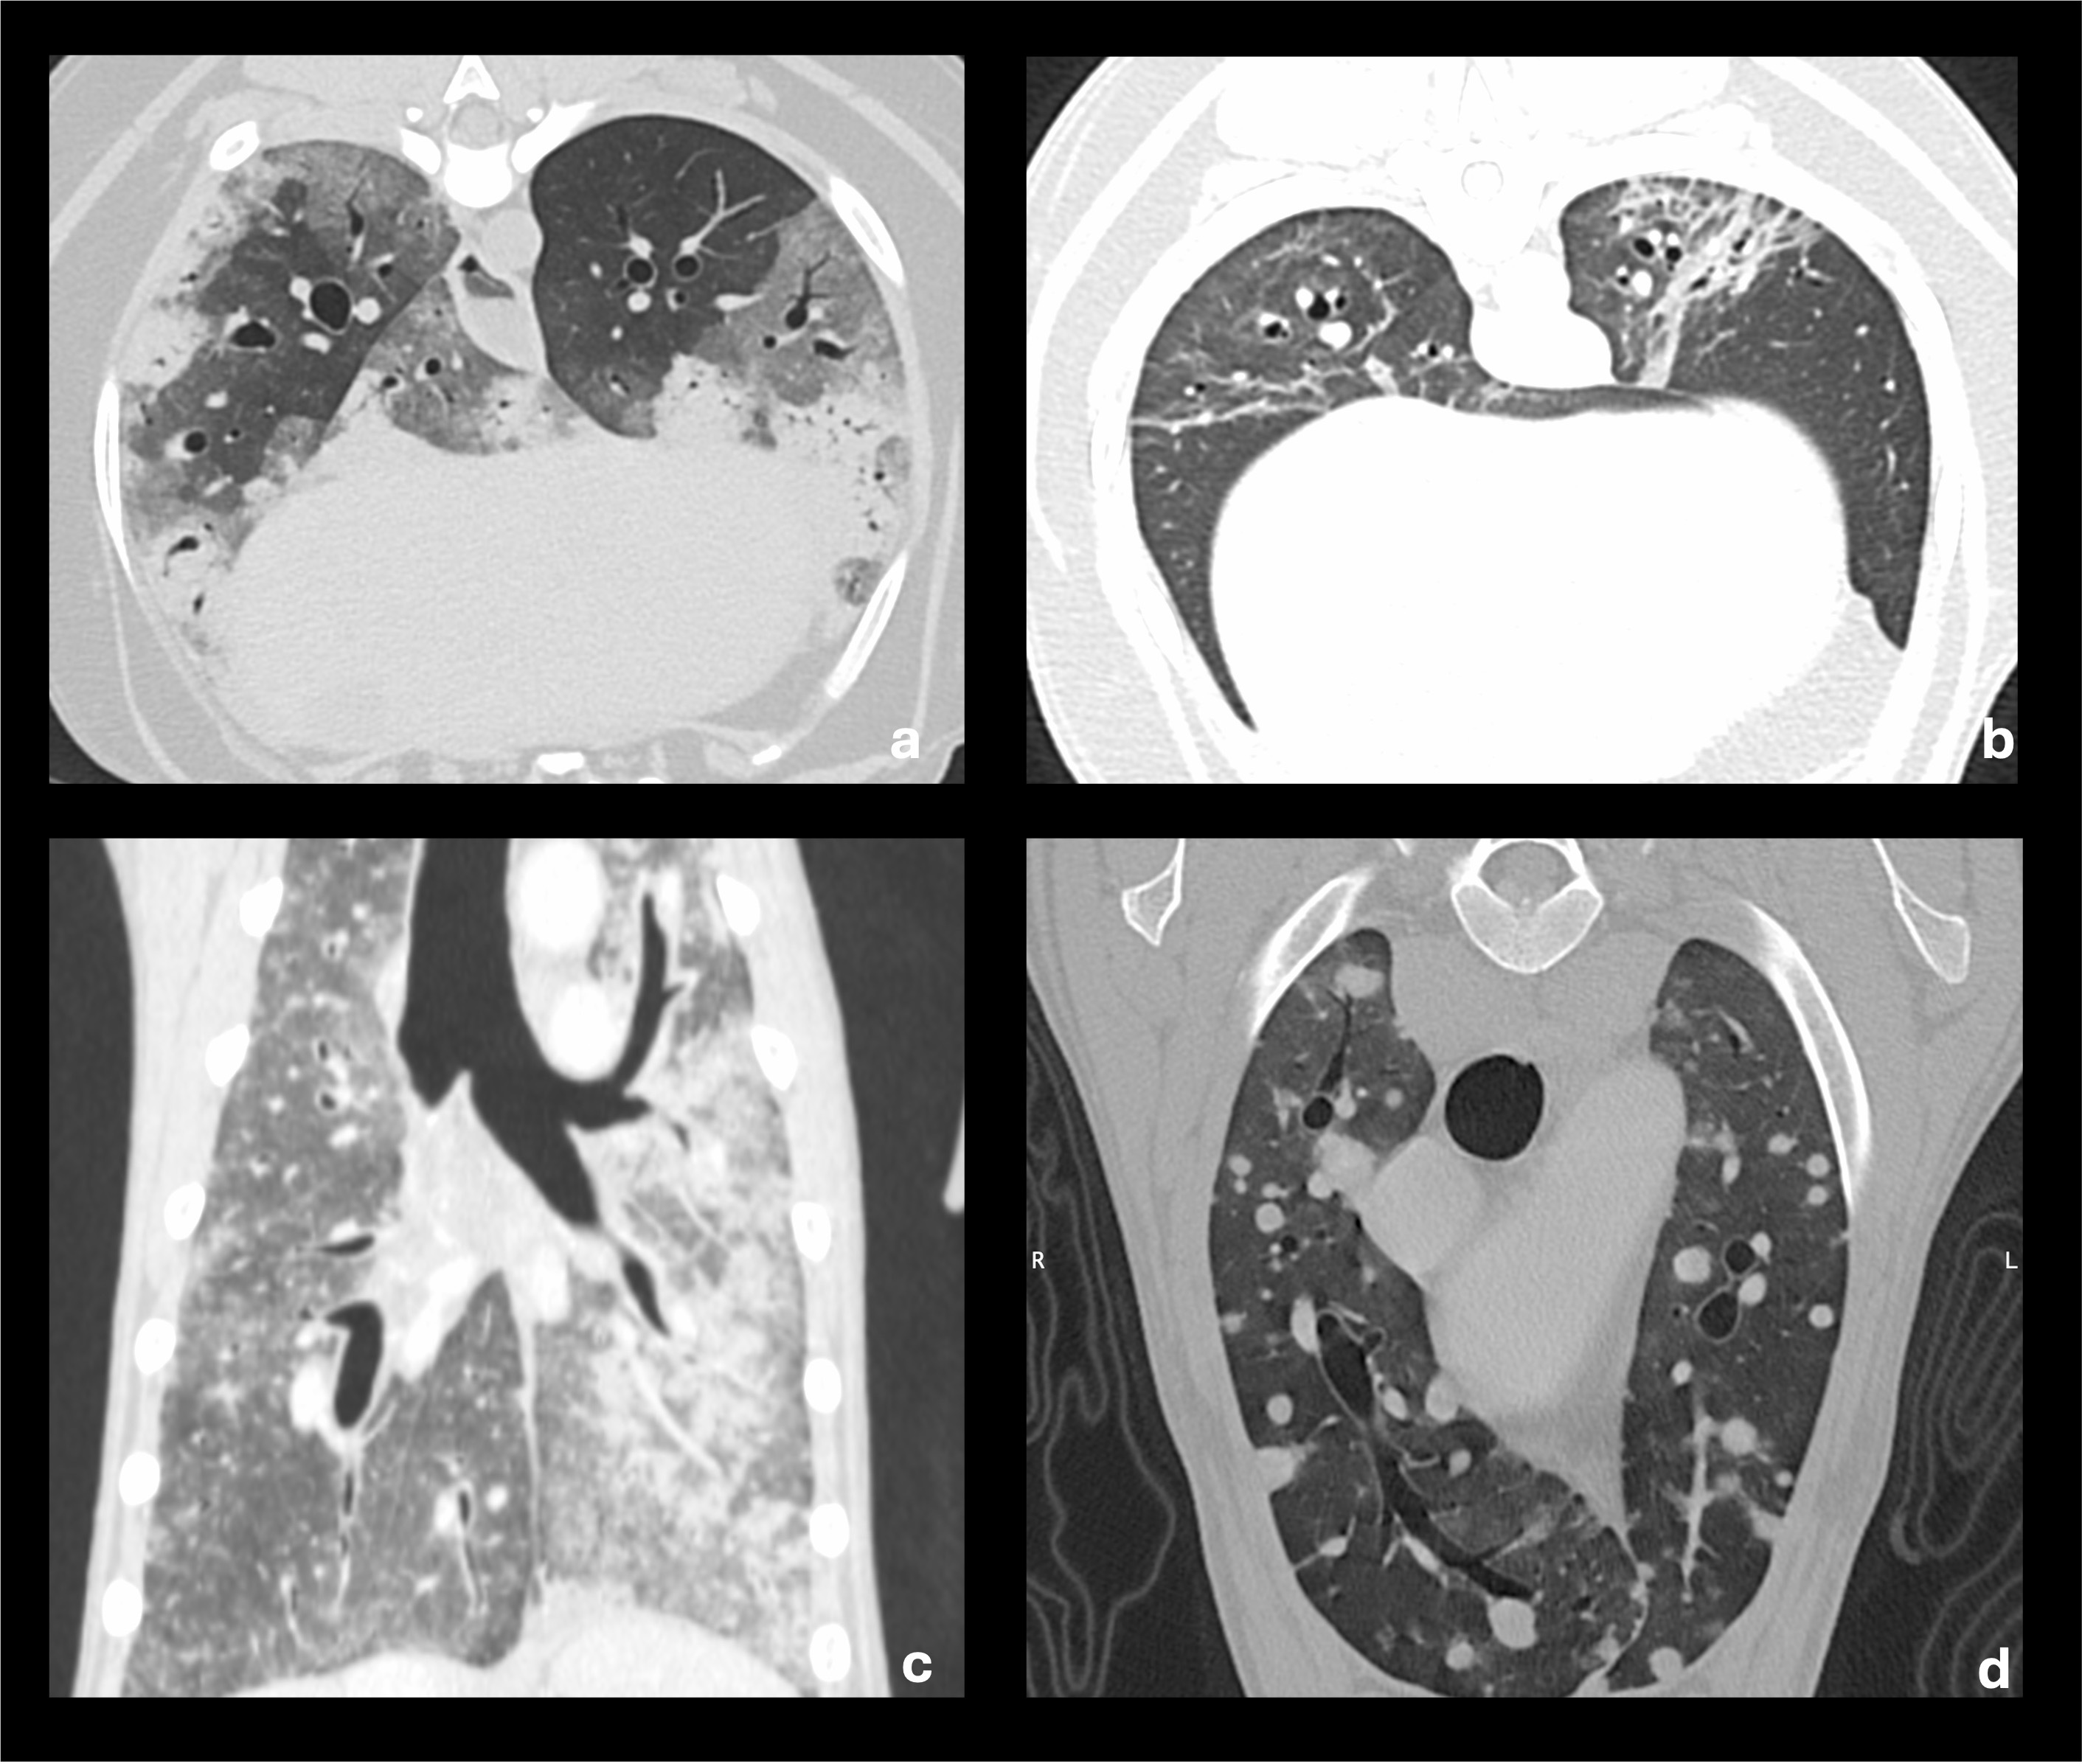

Die CT ist das sensitivste Verfahren zur Beurteilung pulmonaler Veränderungen beim Hund und stellt den diagnostischen Referenzstandard für Parenchymerkrankungen, Atemwegspathologien und das onkologische Staging dar. Durch die überlagerungsfreie Darstellung lassen sich selbst millimetergroße Läsionen sicher detektieren und charakterisieren.

Ein wesentlicher Vorteil der CT liegt in der morphologischen Subklassifikation von Veränderungen, die im Röntgen lediglich als „interstitiell“ imponieren. Ground-glass-Opazitäten, Konsolidierungen, retikuläre Veränderungen oder endobronchiale Muster (z. B. „tree-in-bud“) lassen sich differenzieren und klinisch einordnen (Abb. 2). Dies ist entscheidend für die Abgrenzung zwischen entzündlichen, ödematösen, hämorrhagischen oder atelektatischen Prozessen.

Ein wichtiger Interpretationsaspekt ist die lagerungs- und narkosebedingte Atelektase, die vor allem in abhängigen Lungenarealen auftritt und entzündliche Veränderungen vortäuschen kann. Standardisierte CT-Protokolle, kurze Atemstillstände und eine bewusste Bewertung der Verteilungsmuster sind essenziell, um Fehldiagnosen zu vermeiden. In Tabelle 2 finden sich verschiedene CT-Befunde mit den markanten morphologischen Merkmalen und der klinischen Interpretation.

Limitationen der CT sind der Einsatz von Narkosen, Bewegungsartefakte bei unzureichender Atemkontrolle sowie Kosten und Verfügbarkeit. In der Regel sollte bei onkologischen Fragestellungen, Gefäß- und Mediastinalbeurteilung oder zur Abgrenzung komplexer Läsionen ein Scan nach Kontrastmittelgabe ergänzend zur nativen Untersuchung durchgeführt werden.